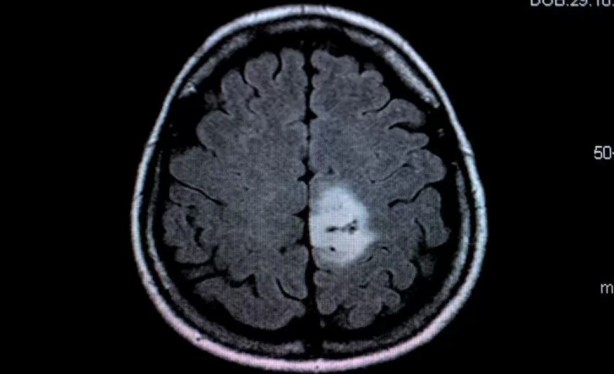

Open AI'ın ürettiği yapay zeka ChatGPT, beyin tümörlerinin teşhisinde radyologlardan daha iyi sonuçlar vermeyi başardı.

OpenAI'nin GPT-4 LLM'sine dayanan bir yapay zeka modeli olan ChatGPT, beyin tümörlerinin teşhisinde etkileyici beceriler gösteriyor. Osaka Metropolitan Üniversitesi Tıp Fakültesi'nden araştırmacılar, 150 ameliyat öncesi beyin tümörü MR raporunu kullanarak ChatGPT ile radyologların tanı doğruluğunu karşılaştıran bir çalışma yürüttüler.

Sonuçlar ise oldukça şaşırtıcı. ChatGPT yüzde 73'lük bir puan alarak nöroradyologların (yüzde 72) ve genel radyologların (yüzde 68) doğruluk oranını geride bıraktı.